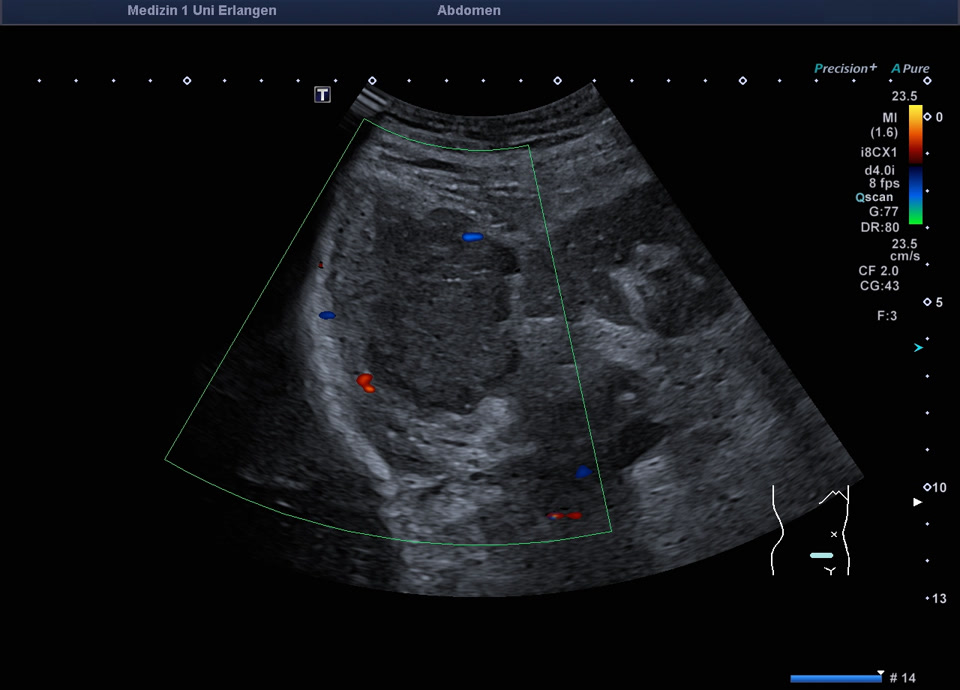

• Subcutaneous metastasis (color Doppler, video)

• Subcutaneous metastasis (color Doppler)

• Psoas metastasis of urothelial carcinoma (color Doppler)